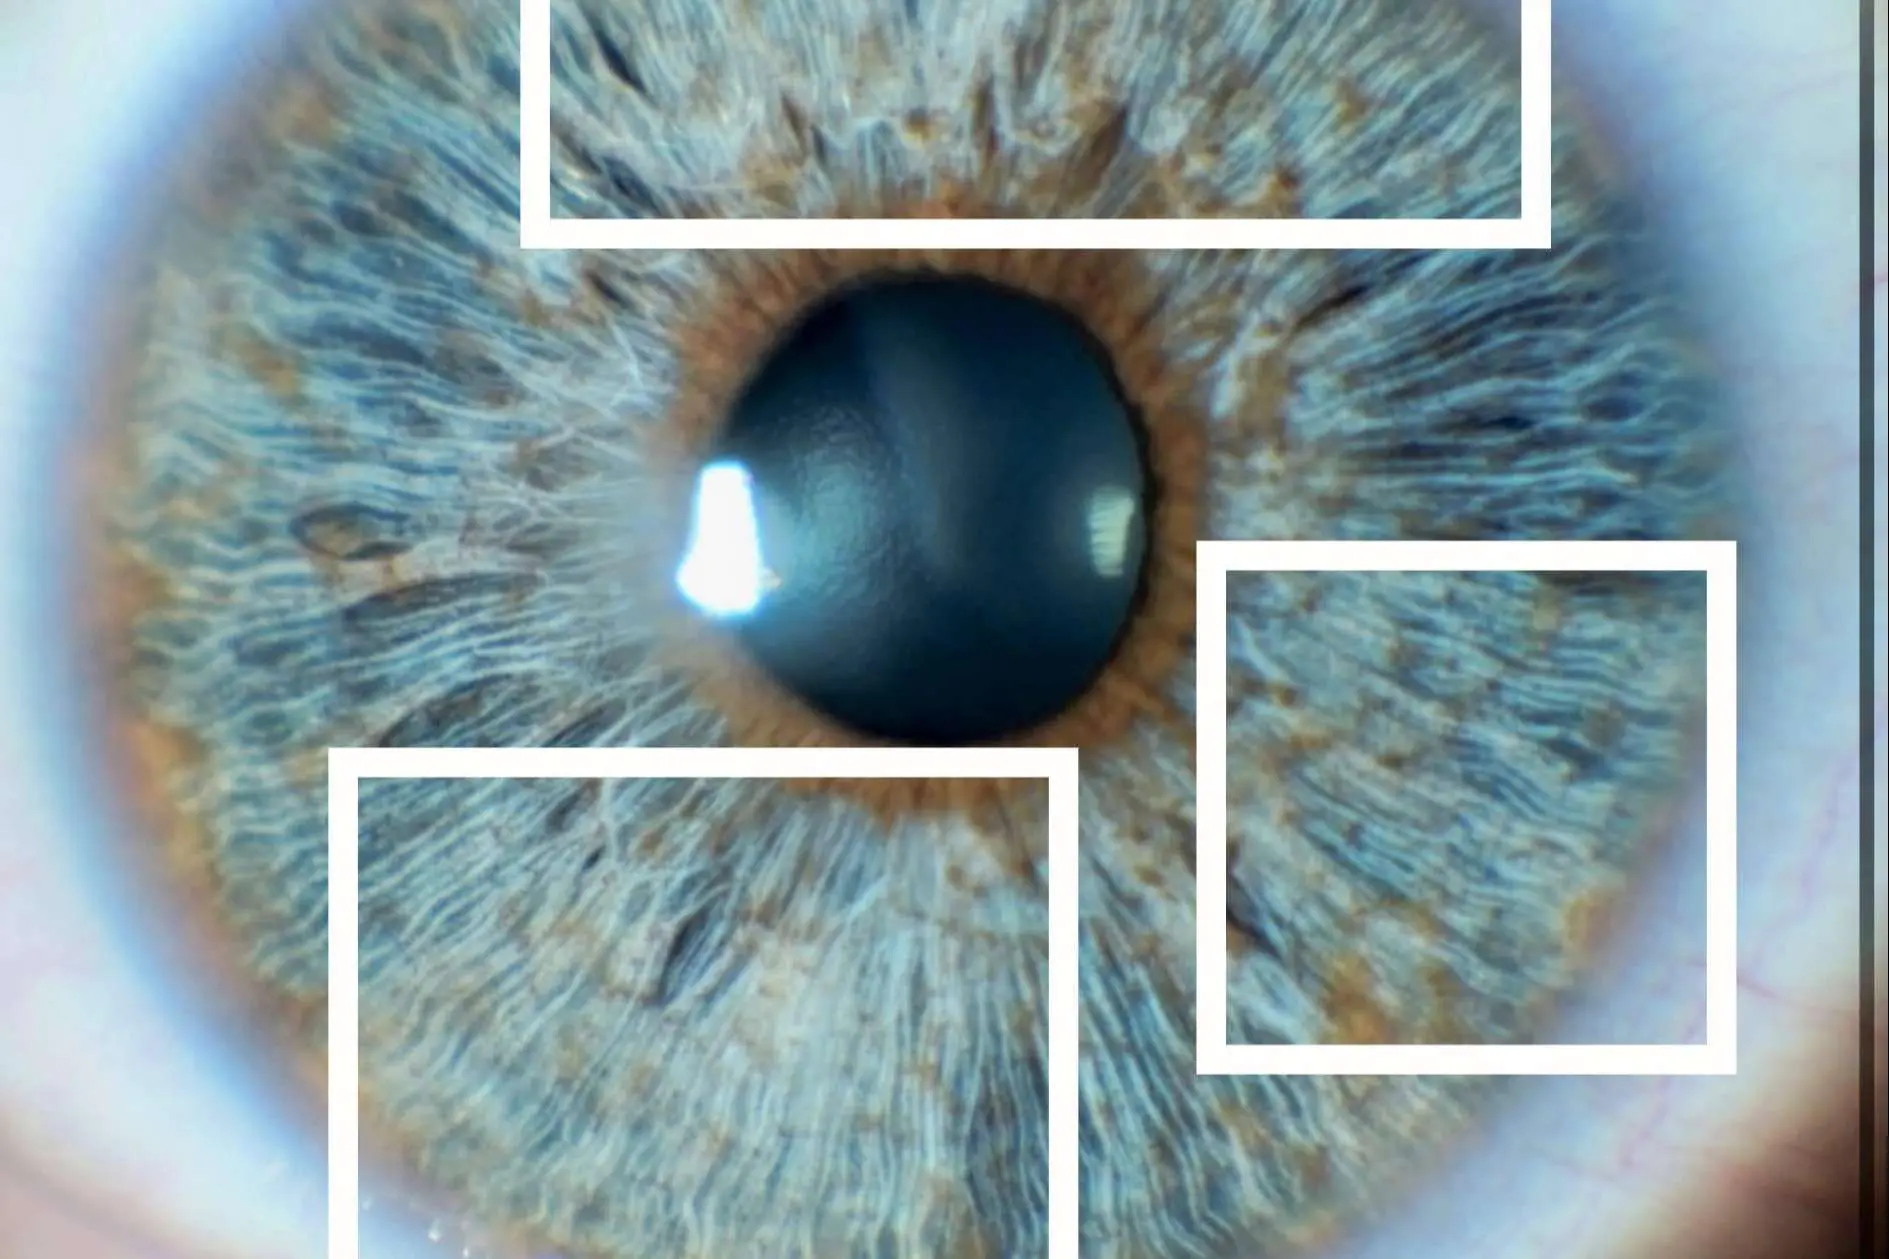

Antes de realizar la iridoplastia láser, en Eyecos califican el iris en 5 grados distintos, dependiendo de la cantidad de melanina presente en el iris. Se utiliza una escala de pigmentación de 1 a 5, donde el grado 1 representa ojos más claros con menos pigmento, y el grado 5 denota colores más oscuros y mayor pigmentación. Independientemente de ello, en los grados 2 y 3, también se puede evaluar la densidad de colágeno de sus pacientes. Sin embargo, en ojos muy oscuros (grado 4 y 5), el colágeno se encuentra oculto detrás de la melanina, lo que dificulta su medición precisa.

La densidad de colágeno en el iris puede influir en el resultado estético de la iridoplastia laser, determinando si el resultado será más brillante o más opaco. Esta información es crucial para que sus pacientes comprendan las posibles variaciones en el resultado final de su transformación ocular.

Para ilustrar este concepto, se han incluido imágenes que ejemplifican la diferencia entre un iris con zonas opacas (indicando una menor densidad de colágeno) y un iris con zonas brillantes (indicando una mayor densidad de colágeno). Estas imágenes proporcionan una representación visual de cómo el colágeno puede afectar la apariencia del iris después del tratamiento.